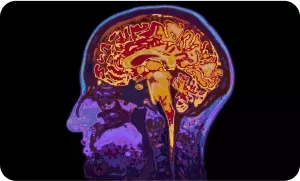

ПЭТ/КТ всего тела с 18-ФДГ является адекватным и высокоинформативным методом первичной диагностики и мониторинга изменений в скелете при опухолях, тропных к 18F-ФДГ. При оценке эффективности противоопухолевого лекарственного лечения методом ПЭТ/КТ с 18F-ФДГ особенно у пациентов с множественными метастазами не только в костях, но и в различных органах, рекомендуется использовать критерии PERSIST и вывод о прогрессировании со стороны метастазов в скелете делать только при выявлении новых очагов в сочетании с повышением уровня накопления РФП на ПЭТ в прогрессирующем очаге по данным КТ. Критериями ПЭТ-ответа при солидных опухолях (по критериям PERCIST) является снижение метаболической активности максимально активного метастаза в кости на 30% и более.

Если по результатам ПЭТ/КТ определяется изолированное изменение активности накопления РФП в ранее имевшихся очагах, то возможно интерпретировать это как процессы репарации.

ПЭТ/КТ всего тела с 18-ФДГ является адекватным и высокоинформативным методом первичной диагностики и мониторинга изменений в скелете при опухолях, тропных к 18F-ФДГ.

При оценке эффективности противоопухолевого лекарственного лечения методом ПЭТ/КТ с 18F-ФДГ особенно у пациентов с множественными метастазами не только в костях, но и в различных органах, рекомендуется использовать критерии PERSIST и вывод о прогрессировании со стороны метастазов в скелете делать только при выявлении новых очагов в сочетании с повышением уровня накопления РФП на ПЭТ в прогрессирующем очаге по данным КТ. Критериями ПЭТ-ответа при солидных опухолях (по критериям PERCIST) является снижение метаболической активности максимально активного метастаза в кости на 30% и более.